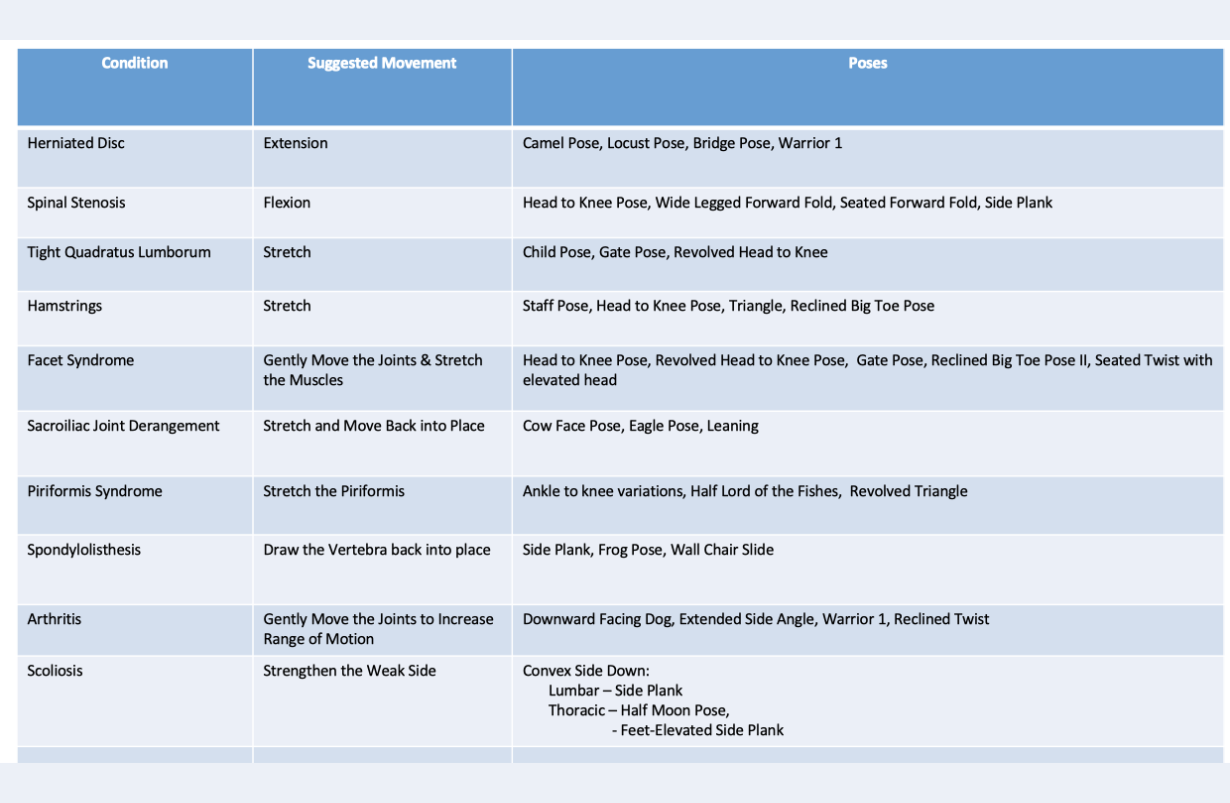

Low back pain is not a diagnosis. It is a symptom. Different conditions can cause the very same symptoms, even though these underlying conditions may have opposite treatments, and what is good for one of these conditions is bad for the other. For example, herniated disc and spinal stenosis may produce exactly the same symptoms: back pain calf tingling and pain going down the back of the leg, but they have diametrically opposite treatments: back bends for herniated disc and forward bends for spinal stenosis. Moreover, back bends usually worsen the pain of spinal stenosis, and forward bends can actually extend a herniated disc, making things permanently worse. There are essentially seven major causes of lower back pain. They fit into three categories: Neurological: Herniated lumbar disc Spinal stenosis Musculoskeletal: Quadratus lumborum spasm Facet syndrome Sacroiiac joint derangement Mixed: Piriformis syndrome Spondylolisthesis The neurological causes produce numbness, tingling, weakness and/or sciatic pain The musculoskeletal have none of these features, but are often painful to the touch. The mixed group have neurological symptoms that are caused by a muscular or skeletal abnormality that affects a nerve or nerve root. More detail is given in the images below.